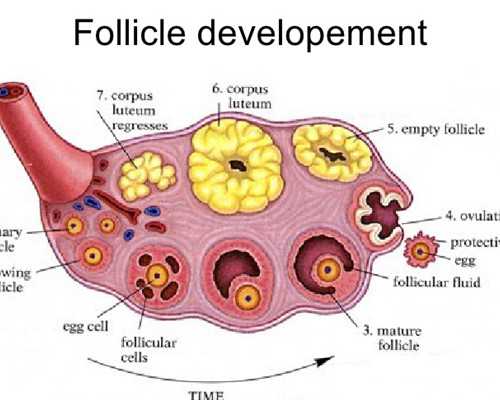

這當(dāng)中主要原因是卵子質(zhì)量與卵巢功能的退化而引起,再加上環(huán)境污染、輻射、化學(xué)品等多種不良因素影響,卵子質(zhì)量無時(shí)不刻的發(fā)生著退化與改變。

美國(guó)試管嬰兒恩西諾分院RobertBoostanfar[羅伯特布斯坦福]說:據(jù)多年臨床調(diào)查,卵巢的儲(chǔ)備功能在30-35歲以后便開始迅速下降。同時(shí),如果在35歲之前曾有多次懷孕流產(chǎn)、第一胎不健康經(jīng)歷,更會(huì)增加二胎風(fēng)險(xiǎn)和不孕不育的幾率。

? ? 對(duì)于高齡女性生育的困難,泰國(guó)試管嬰兒會(huì)根據(jù)高齡女性的身體情況制定適合的方案,合理促排,科學(xué)使用促排卵藥物控制性促排,減少對(duì)女性身體的傷害,這樣即使是高齡生育也不會(huì)對(duì)身體有太多的傷害,取得高質(zhì)量的卵子,增大試管嬰兒的成功率。在促排時(shí)會(huì)嚴(yán)格監(jiān)控和及時(shí)調(diào)整,在卵泡發(fā)育成熟及時(shí)取出,獲得多顆卵子,因?yàn)楦啐g生育的女性卵泡少,所以科學(xué)促排非常重要。